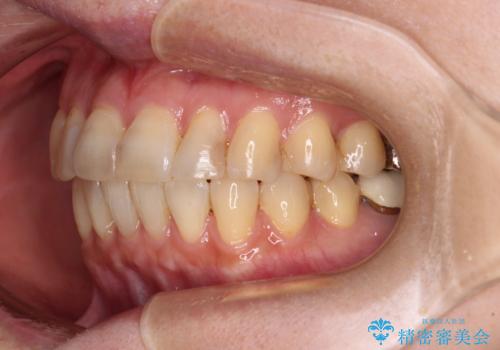

- 40代女性

- 矯正装置

- 審美装置

- 前歯のデコボコを気にして来院された患者様です。

インビザラインでもワイヤー装置でも対応可能であったので、両者のデメリットをご説明し、選択していただくことになりました。

マウスピース矯正の装着時間の長さや自己管理の重要性を煩わしいと感じられ、低依存で確実に治療ができるワイヤー矯正を選択されました。

舌突出癖により、上下前歯がなかなか接触せずに治療期間を要しましたが、舌のトレーニングにより無事に治療を終えることができました。